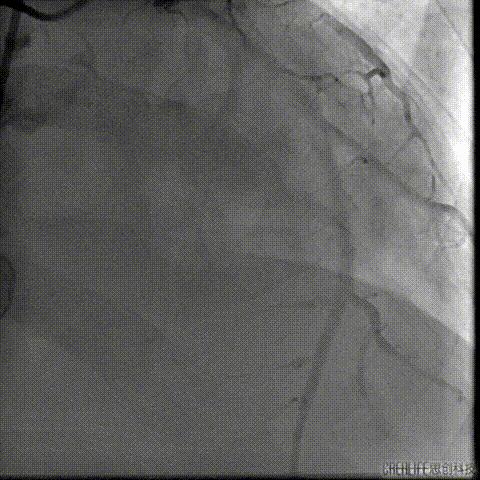

冠脉造影

瓣上造影

猪尾导管位于右窦

严重反流导致造影效果欠佳

左冠显示不清 结构显示不清